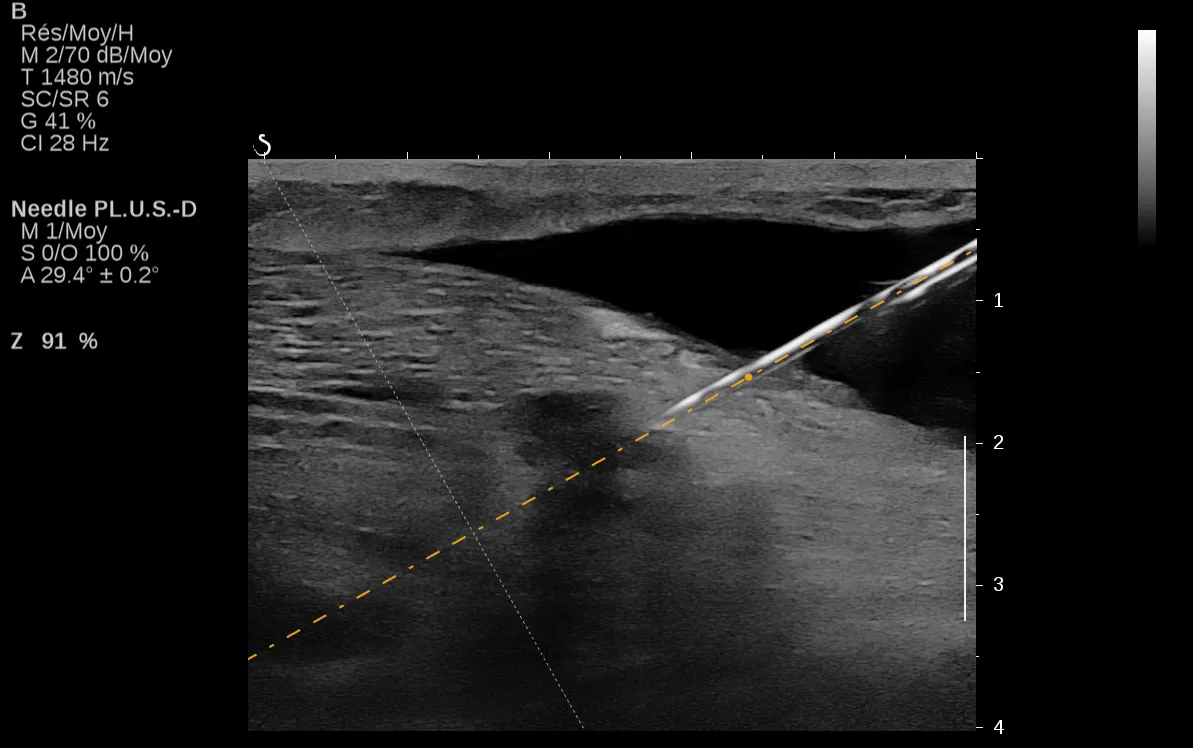

The Aixplorer Ultimate ultrasound unique capabilities of Shearwave Elastography, are going to be presented in the workshop which will be held on 29/9/2018, during the ultrasound – elastography workshop.

Find out how SWE can help you increase the sensitivity of the ultrasound exam, the biopsy predictive value, and how a DCIS can be upgraded to IDC.